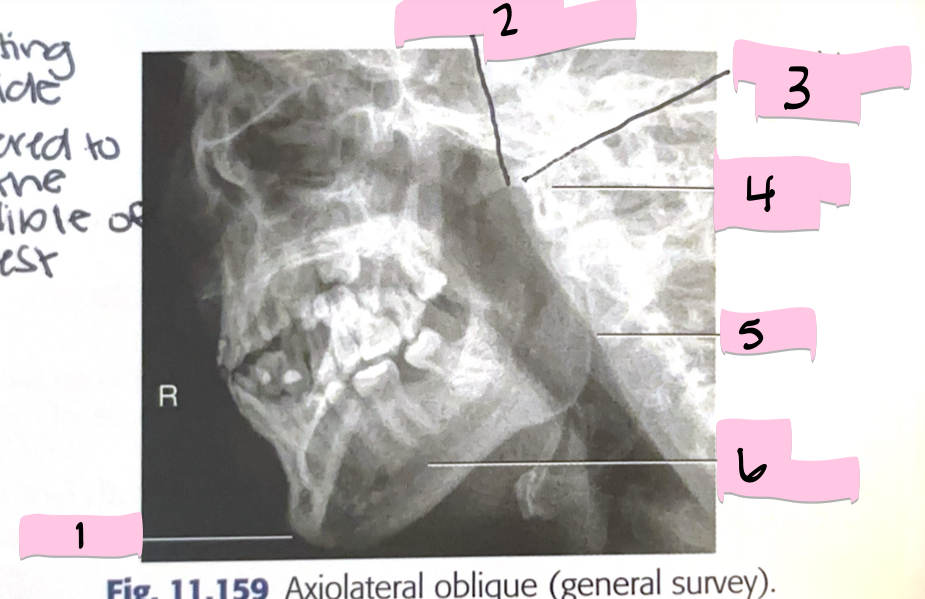

What is 1 pointing to?

Mentum

What is 2 pointing to?

Coranoid process

What is 3 pointing to?

Mandibular notch

What is 4 pointing to?

Condyloid process

What is 5 pointing to?

Ramus

What is 6 pointing to?

Body